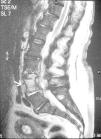

Se trata de una mujer de 69 años con antecedentes de diabetes mellitus tipo 2, mastectomía radical izquierda por carcinoma de mama, que recibió quimioterapia, radioterapia y hormonoterapia con tamoxifemo. Se encontraba en tratamiento con insulina NPH y tamoxifeno. Acudió al servicio de Urgencias de un hospital de nuestra área sanitaria con clínica de dolor lumbar de 5 días de duración. Había presentado leucocoria de ojo izquierdo en las últimas 48 horas. En la exploración física presentaba temperatura de 37 ºC, leucocoria de ojo izquierdo y dolor a la palpación sobre las últimas vértebras lumbares. La tensión arterial era de 160/90 mmHg, frecuencia cardíaca 110 latidos/minuto y frecuencia respiratoria de 28 respiraciones/minuto. La analítica mostró: hemoglobina: 12,3 g/dl, hematocrito: 34,5%, leucocitos: 16.900/mm3 (el 95% segmentados, el 3% cayados), plaquetas: 67.000/mm3, actividad de protrombina: 83%, tiempo de cefalina: 29 seg, glucosa: 576 mg/dl, urea: 122 mg/dl, creatinina: 1,2 mg/dl. La gasometría arterial (fracción inspirada de oxígeno [FiO2] 0,35) mostró: pH: 7,42, presión parcial de dióxido de carbono arterial (PaCO2): 37 mmHg, presión parcial de oxígeno arterial (PaO2): 81 mmHg, bicarbonato: 24 mEq/l. En el sedimento de orina destacaba intensa bacteriuria. La radiografía de tórax fue normal. Durante su estancia en Urgencias sufrió deterioro neurológico por lo que se realizó una tomografía axial computarizada de cráneo que no demostró patología intracraneal, presentando aumento de la densidad de cristalino izquierdo. Se realizó punción lumbar que resultó de aspecto purulento con resultado siguiente: leucocitos: 168.000 mm3 (el 83% segmentados), glucosa: 43 mg/dl, proteínas: 2.350 mg/dl y cocos grampositivos. Se diagnosticó de meningitis e infección del tracto urinario y se trasladó a nuestra Unidad de Cuidados Intensivos (UCI). Se inició terapia antibiótica empírica con ceftriaxona y vacomicina. Ante la presencia de importante dolor lumbar se realizó resonancia magnética nuclear (RMN) de columna dorso-lumbar que evidenció la presencia de espondilitis a nivel de L4 y L5 con una colección en espacio epidural compatible con absceso epidural (fig. 1) y afectación de ambos músculos psoas (fig. 2). Fue intervenida con desbridamiento de los abscesos de músculos psoas tomando muestras para análisis microbiológico. También se obtuvieron muestras de humor vítreo y se instilaron antibióticos intraoculares. Se aisló en cultivo de líquido cefalorraquídeo, hemocultivos, cultivo de orina, humor vítreo y muestras de pus de psoas S. agalactiae sensible a penicilina, por lo que se sustituyó el tratamiento antibiótico mencionado por penicilina G endovenosa; por parte de oftalmología se instauró tratamiento con vancomicina y ceftriaxona en colirio.

Figura 2. Resonancia magnética nuclear mostrando la afectación de ambos músculos psoas.